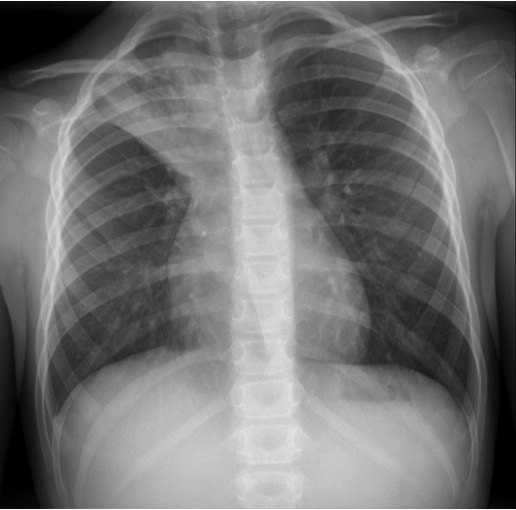

CASO: Pediátrico de más de 2 años tratado por porceso oncológico que ha comenzado con febricula y tos.

Hallazgos:

- Parénquimas pulmonares y silueta cardiomediatínica sin alteraciones significativas. No hay foco neumónico.

- Catéter reservorio subcutáneo con extremo distal en aurícula derecha.

- Resección de la porción anterior de la 6ª costilla. Suponemos que es ahí donde radicaba su proceso de base